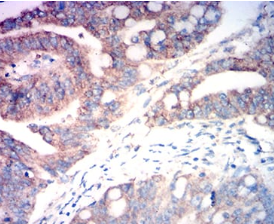

IHC    1/200 - 1/1000